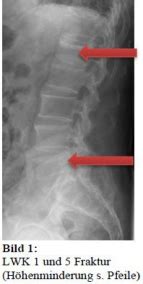

This kind of fracture can happen due to a variety of reasons, ranging from high-impact trauma (like a car accident or a fall from a significant height) to more subtle causes such as osteoporosis, which weakens the bones, making them more susceptible to breaks. The nature of the fracture can vary, from simple cracks to more complex breaks involving multiple fragments. The specifics depend on the force involved and the overall health of the bone. Diagnosing it typically involves imaging techniques such as X-rays, CT scans, or MRI scans to visualize the fracture and assess the extent of the damage. Treatment options also vary, and that depends on the severity of the fracture, but can include anything from rest and pain management to more invasive procedures such as surgery to stabilize the spine.

• X-rays : X-rays are often the first step in diagnosing a fracture. They can show the basic structure of the bones and help identify breaks.

• CT scans : If the X-rays aren’t enough, a CT scan might be used. CT scans provide more detailed images, which can reveal the extent of the fracture and any damage to surrounding tissues.